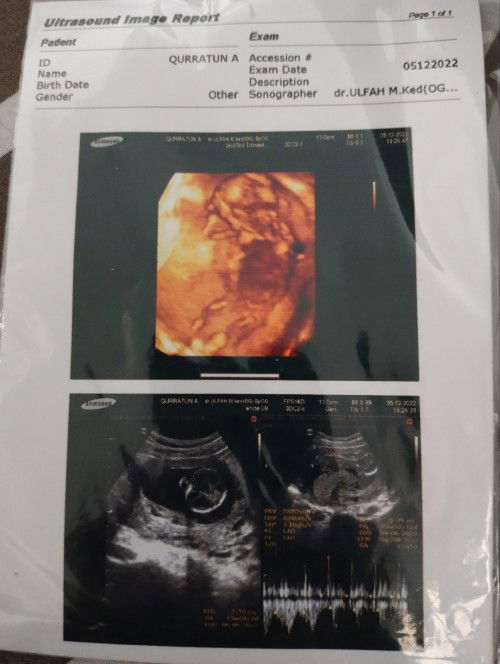

Lahiran secara induksi lewat HPL 8 hari

Alhamdulillah telah lahir anak ke 2 saya berjenis kelamin perempuan dgn berat 3,3 kg dgn cara di induksi krn lewat 8 hari dri HPL. Subhanallah..rupanya begini rasanya diinduksi dgn sakit yg sangat luar biasa saya rasakan sampai saya ingin menyerah tp Allah kasih kekuatan utk melahirkannya #masyaaAllahTabarakallah